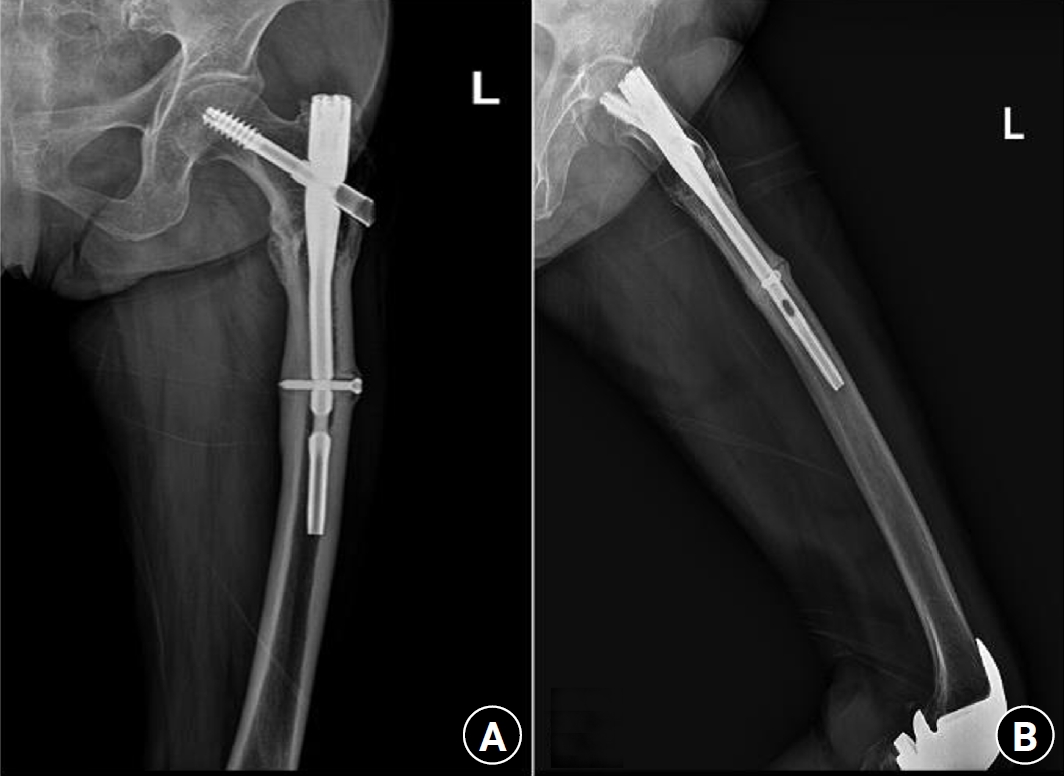

Previous studies have extensively examined the association between femoral insufficiency fractures and prolonged bisphosphonate therapy. However, alternative etiologies remain insufficiently characterized. This study aimed to analyze non-pharmacologic factors associated with femoral insufficiency fractures, with particular emphasis on paradoxical cortical hypertrophy and altered biomechanical load distribution. We reviewed three cases of femoral insufficiency fracture that were surgically treated at our institution between January 2018 and January 2022. None of the patients had a history of bisphosphonate use. Clinical histories—including underlying comorbidities, prior surgical procedures, and radiographic findings—were evaluated. Serial radiographs obtained before and after fracture occurrence were analyzed to characterize fracture morphology and associated cortical changes. Case 1 involved a patient with post-traumatic hip synostosis; case 2 involved a patient with osteogenesis imperfecta; and case 3 involved a patient who had previously undergone intramedullary nailing for an intertrochanteric fracture. Lateral femoral bowing and cortical hypertrophy preceded fracture development in two cases, whereas focal cortical hypertrophy at the distal locking screw site was observed in the third case. No history of bisphosphonate therapy was identified in any patient. Fractures developed at sites characterized by increased cortical remodeling and abnormal load concentration. Femoral insufficiency fractures can occur in the absence of bisphosphonate therapy. Paradoxical cortical hypertrophy and altered biomechanical force distribution appear to be important contributing factors. Level of evidence: IV.